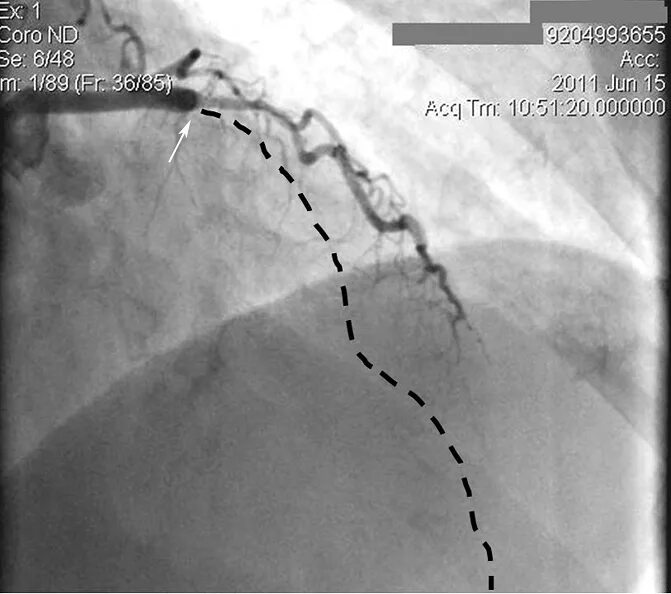

Инфаркт после операции шунтирования